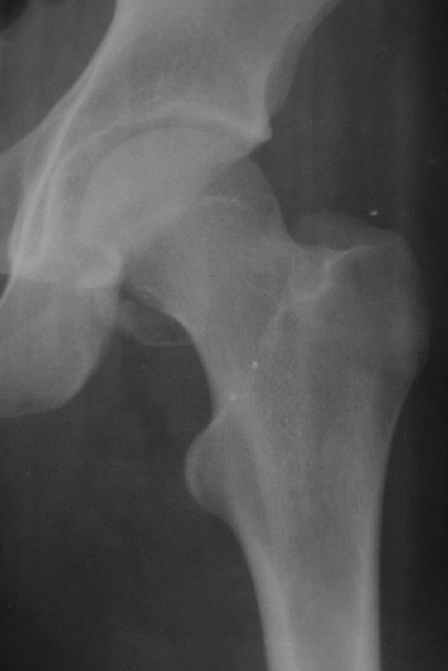

Уважаемые коллеги! Заканчивая обследование больного с переломо-вывихом бедра сделал ему обычные R-томограммы. Кажется удалось "поймать" и отломок и донорское место. Мои выводы - в скиаграмме. Считаю, что это передне-нижний фрагмент головки, образовавшийся вследствии отрывного перелома. На томограммах отломок обозначаю длинной стрелкой, а место откуда он оторвался - более короткой. Учитывая тот факт, что его размеры по КТ 25 х 15 мм считаю, что его фиксация на место необходима для профилактики артроза, что при 16-ти летнем возрасте пациента важно в плане максимального отодвигания эндопротезирования. Планирую оперировать его 24.05.05 г. Результаты представлю.

Прямой при поступлении

Несколько соображений к "картинкам". На прямом снимке и КТ-томограммах все типичные линии вертлужной впадины: крыша, передняя стенка, задняя стенка - сохранены. На КТ-сканах 6 и 7 появляется фрагментация головки. С учетом R-томограмм отломок расположен спереди-снизу, а не сзади-сверху от сустава, как написано в описании КТ.